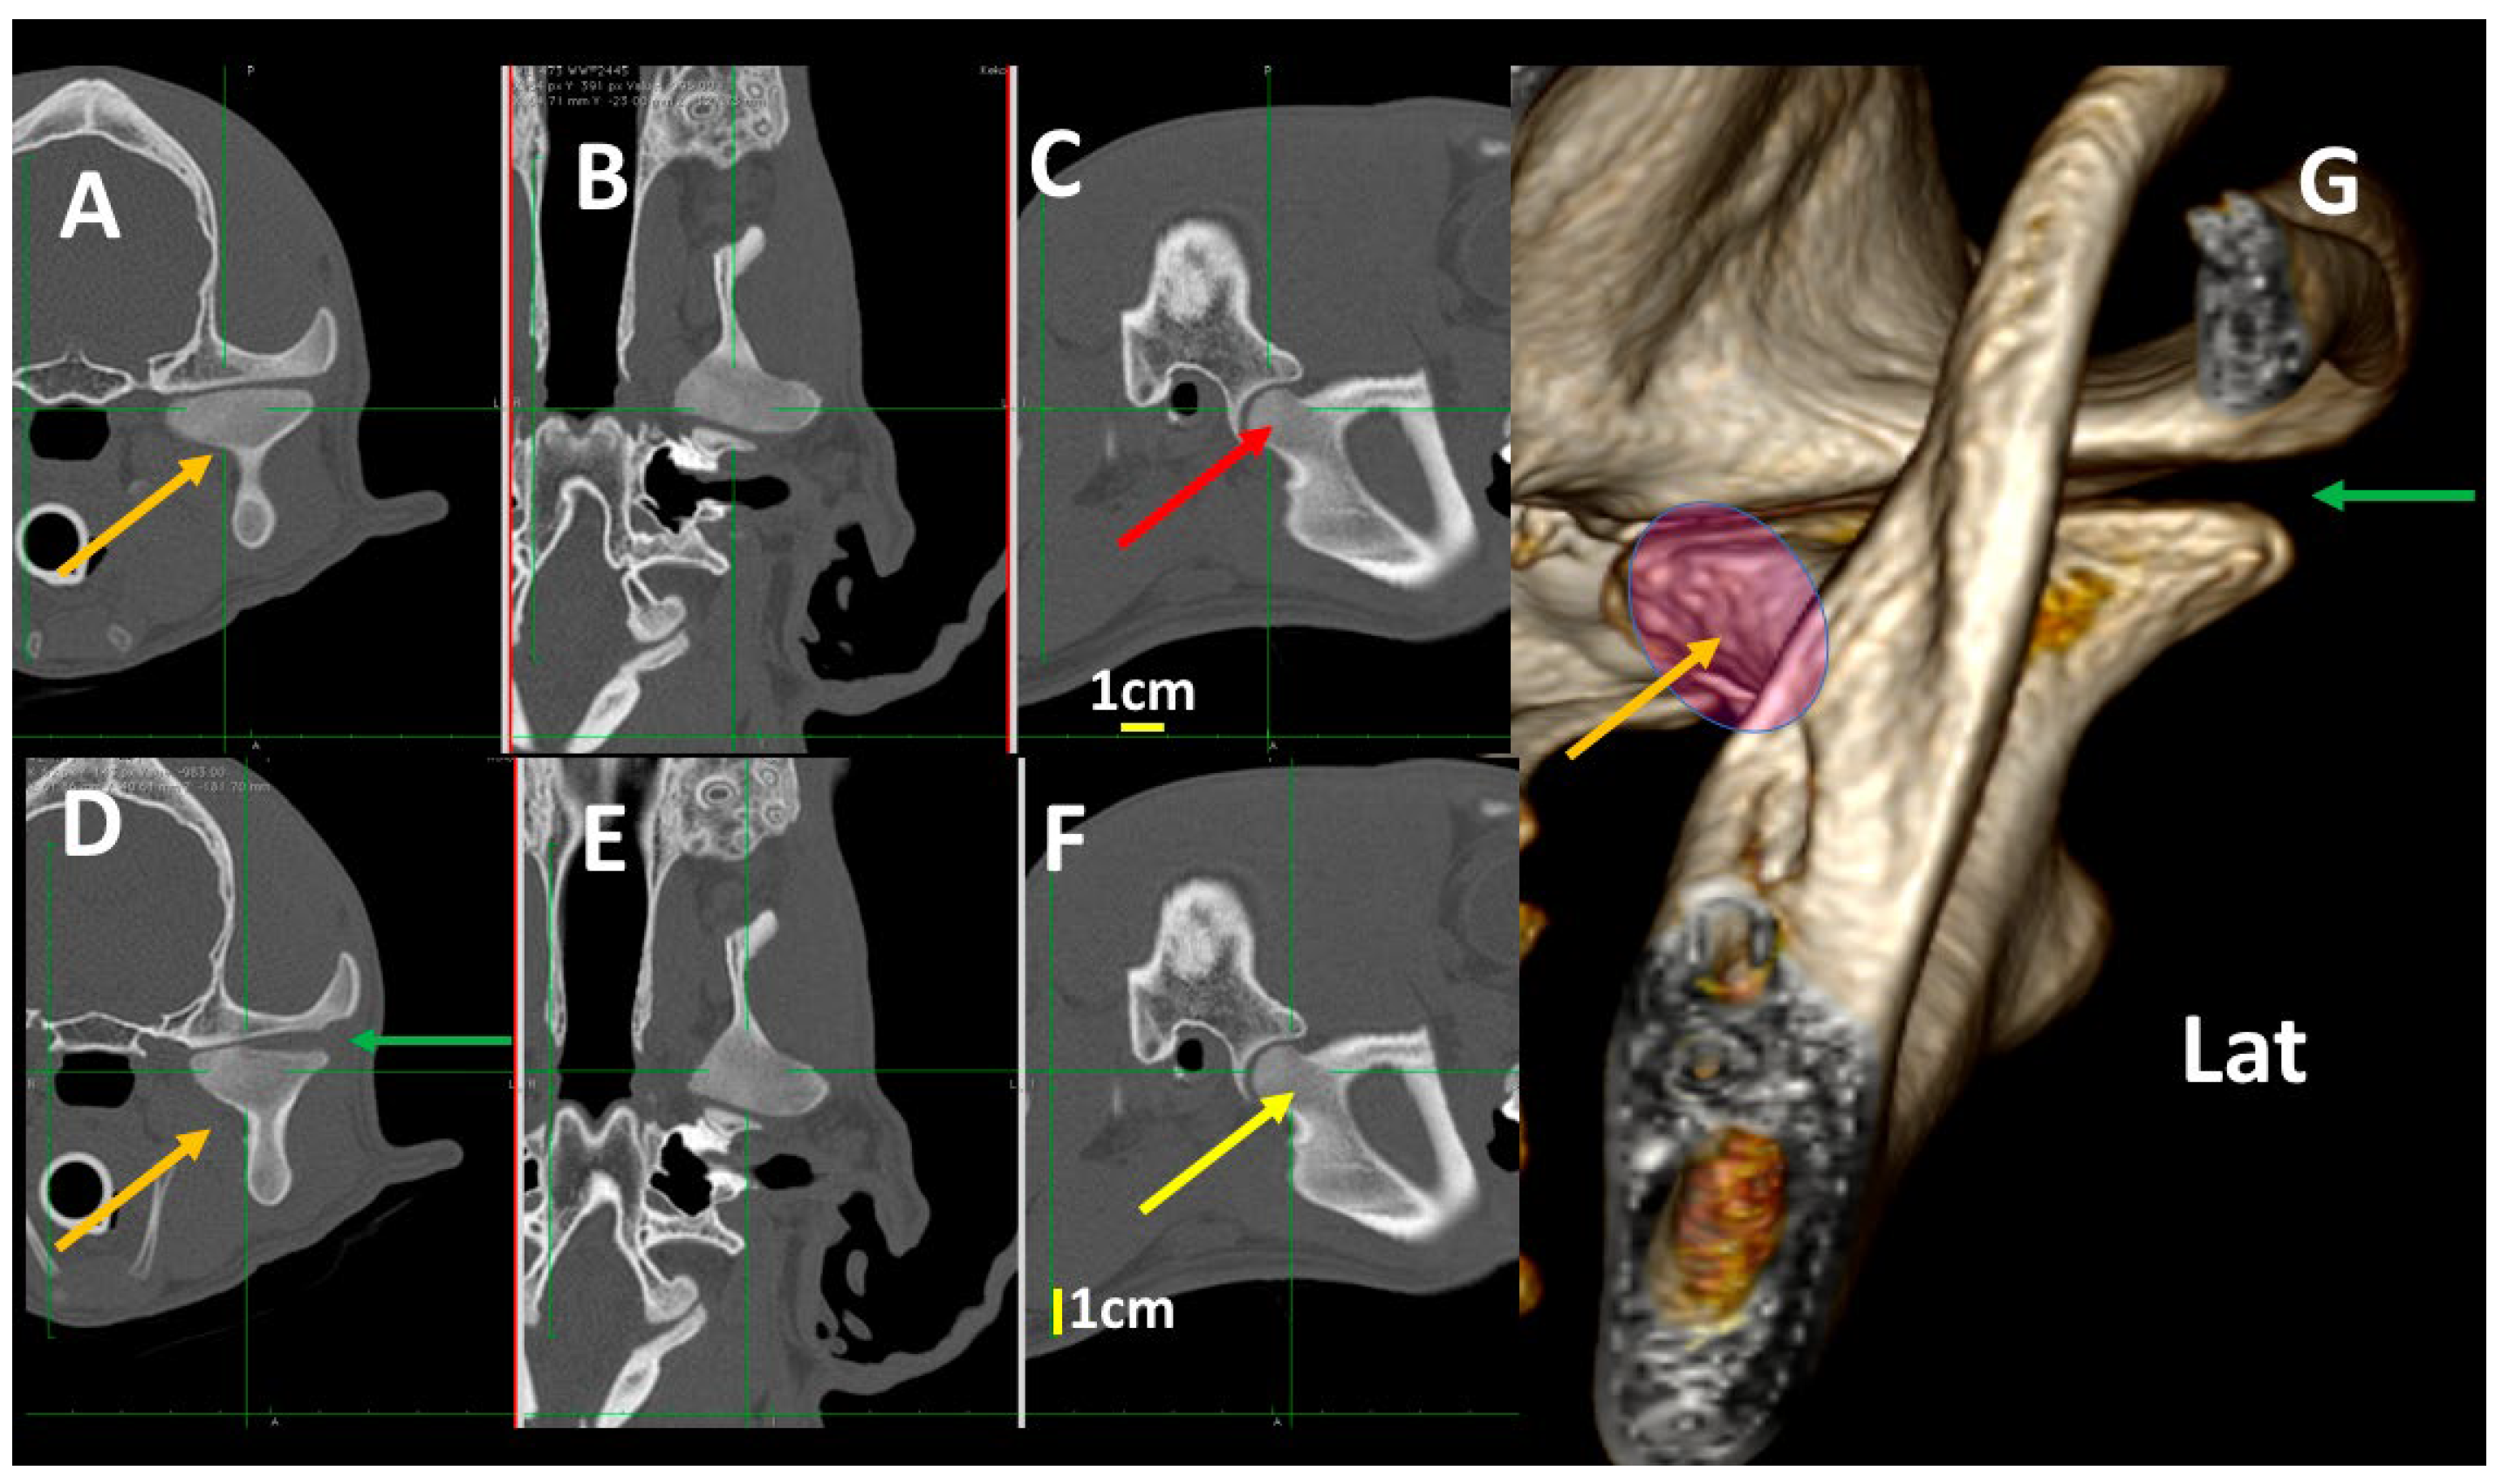

3.3. A Detailed Assessment of Each TMJ Comparing 3DVR Images with the Three Standard CT Planes

3.4. A Pictorial Essay of 3DVR Images in Some Pathological Cases